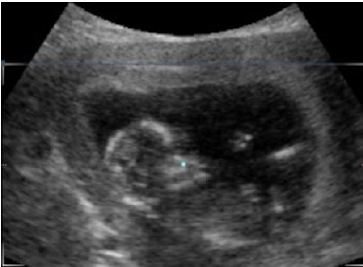

Persistence of the Left Superior Vena Cava with Absence of the Right Superior Vena Cava: Fetal diagnosis and postnatal evolution

Antonio Sánchez Andrés, Reguillo LaCruz A, Gil Beltrán E and Carrasco Moreno JI. 11(11): 10-15.